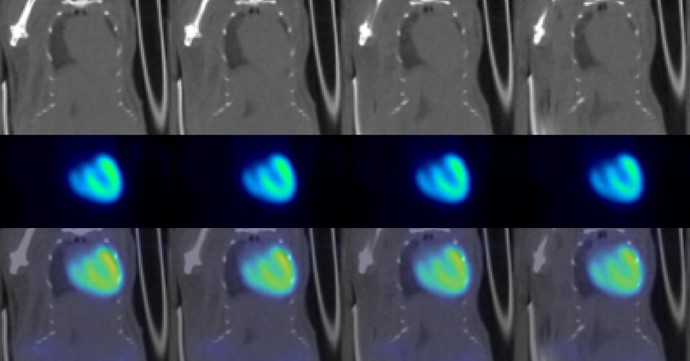

Multi-Animal Dynamic 18FDG-PET/CT in a Mouse Tumor Model

Dynamic PET with low dose injection: 3 MBq 18FDG